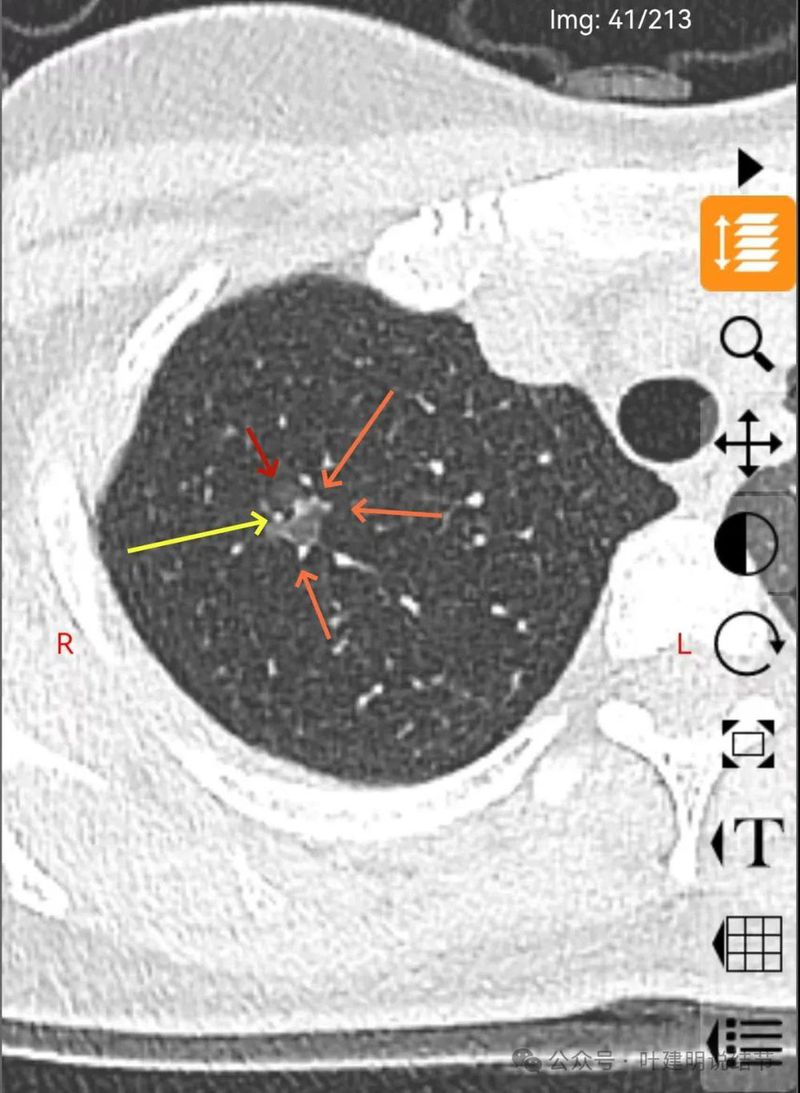

分叶状明显,支气管扩张明显,血管弯征可见,整体轮廓清。

灶内支气管扩张,附近血管有异常增粗,表面不平。

形态不规则、轮廓与边界清、多支血管进入穿行、支气管扩张,表面不平。